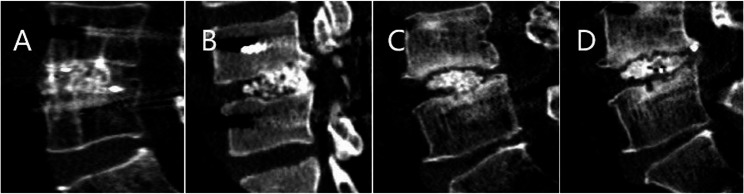

Results: Basic demographic data, fusion rates, postoperative hospital stays, and follow-up times did not significantly differ between the two groups. Compared with those in the M-TLIF group, the intraoperative blood loss (68.57 ± 14.84 mL) and postoperative drainage volume (33.93 ± 9.17 mL) in the M-MIDLIF group were lower (intraoperative blood loss: 171.79 ± 12.78 mL, p < 0.05; postoperative drainage volume: 65.36 ± 10.36, p < 0.05). In the M-MIDLIF group, there was no significant difference in the radiographic recognizable rate (91.07%) or intraoperative visual recognizable rate (87.50%) of internal inverted chevron-shaped (V-shaped) crests. The optimal position screw rates for the MCBT, TASS, and traditional pedicle screw (TPS) methods were 94.64%, 94.64%, and 87.5%, respectively, and the differences were not significant. MCBT technology preserved the integrity of the posterior ligamentous complex (PLC) in 92.85% of patients in the M-MIDLIF group. The facet joint violation (FJV) rate of MCBT screws (3.57%) was lower than that of TPS screws (14.29%). Compared with the M-TLIF group, the M-MIDLIF group presented greater reductions in the ODI and VAS scores for both low back and leg pain at 1 week postoperatively (P < 0.05). However, no statistically significant differences in these scores were observed between the two groups at later time points (p > 0.05).